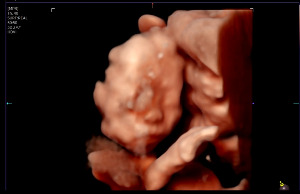

찹쌀이의 뇌, 얼굴, 심장, 폐등 신체의 성장과 이상유무를 확인하고 마지막으로 찹쌀이의 이목구비도

확인해 볼 수 있었다. 아직 선명하진 않지만 눈과 코가 엄마를 닮았네 아빠를 닮았네 하며 즐거워하며

KakaoTalk_20250914_213939247.jpg 24주차 살며시 보이는 찹쌀이의 얼굴